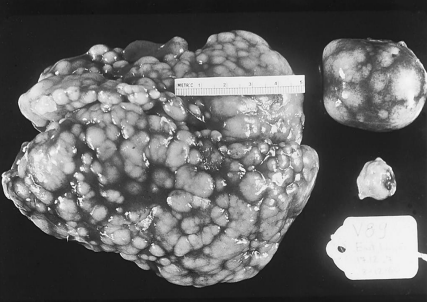

- ์ฌํด์ง๋ฉด bursa์ liver์ enlargement๋ฅผ ์ด์ง์ผ๋ก ์ ์ ์๋ค.

- bursa์ ๊ฑฐ๋ํ๋ nodule๋ ์ง๋จ์ ๋์.

(์ผ์ชฝ์ด liver. ๊ฐ์์ diffuse tumor๊ฐ ๋ํ๋จ. ์ค๋ฅธ์ชฝ์ spleen-focal tumor)

(์ด๋ฐฐ์ค๊ฐ์ tumor์์๋ ๊ฑฐ๋ํ nodule์ด ๊ด์ฐฐ๋จ)